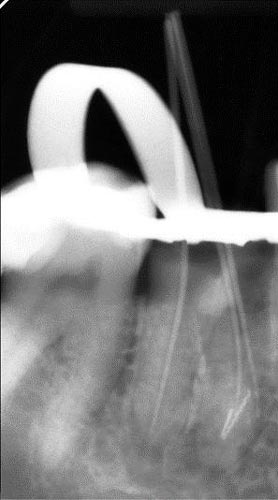

Погляд на сепаровані інструменти. Статистика поломок. Вплив на успішність ендодонтичного лікування. Протокол ухвалення рішення про вилучення уламка. Процедура вилучення за допомогою ультразвуку та альтернативні методики (Ендо ковбой, Петля Тераучі, система Кантервіль, ІРС.). Супутні ускладнення під час вилучення уламків. Мініінвазивна техніка вилучення.

• Методика байпас.

• Теоретичні та практичні методики вилучення (Чи працює те, що показують на лекціях).

• Мінімальний та оптимальний набори інструментів для вилучення.

• Методика Тераучі.